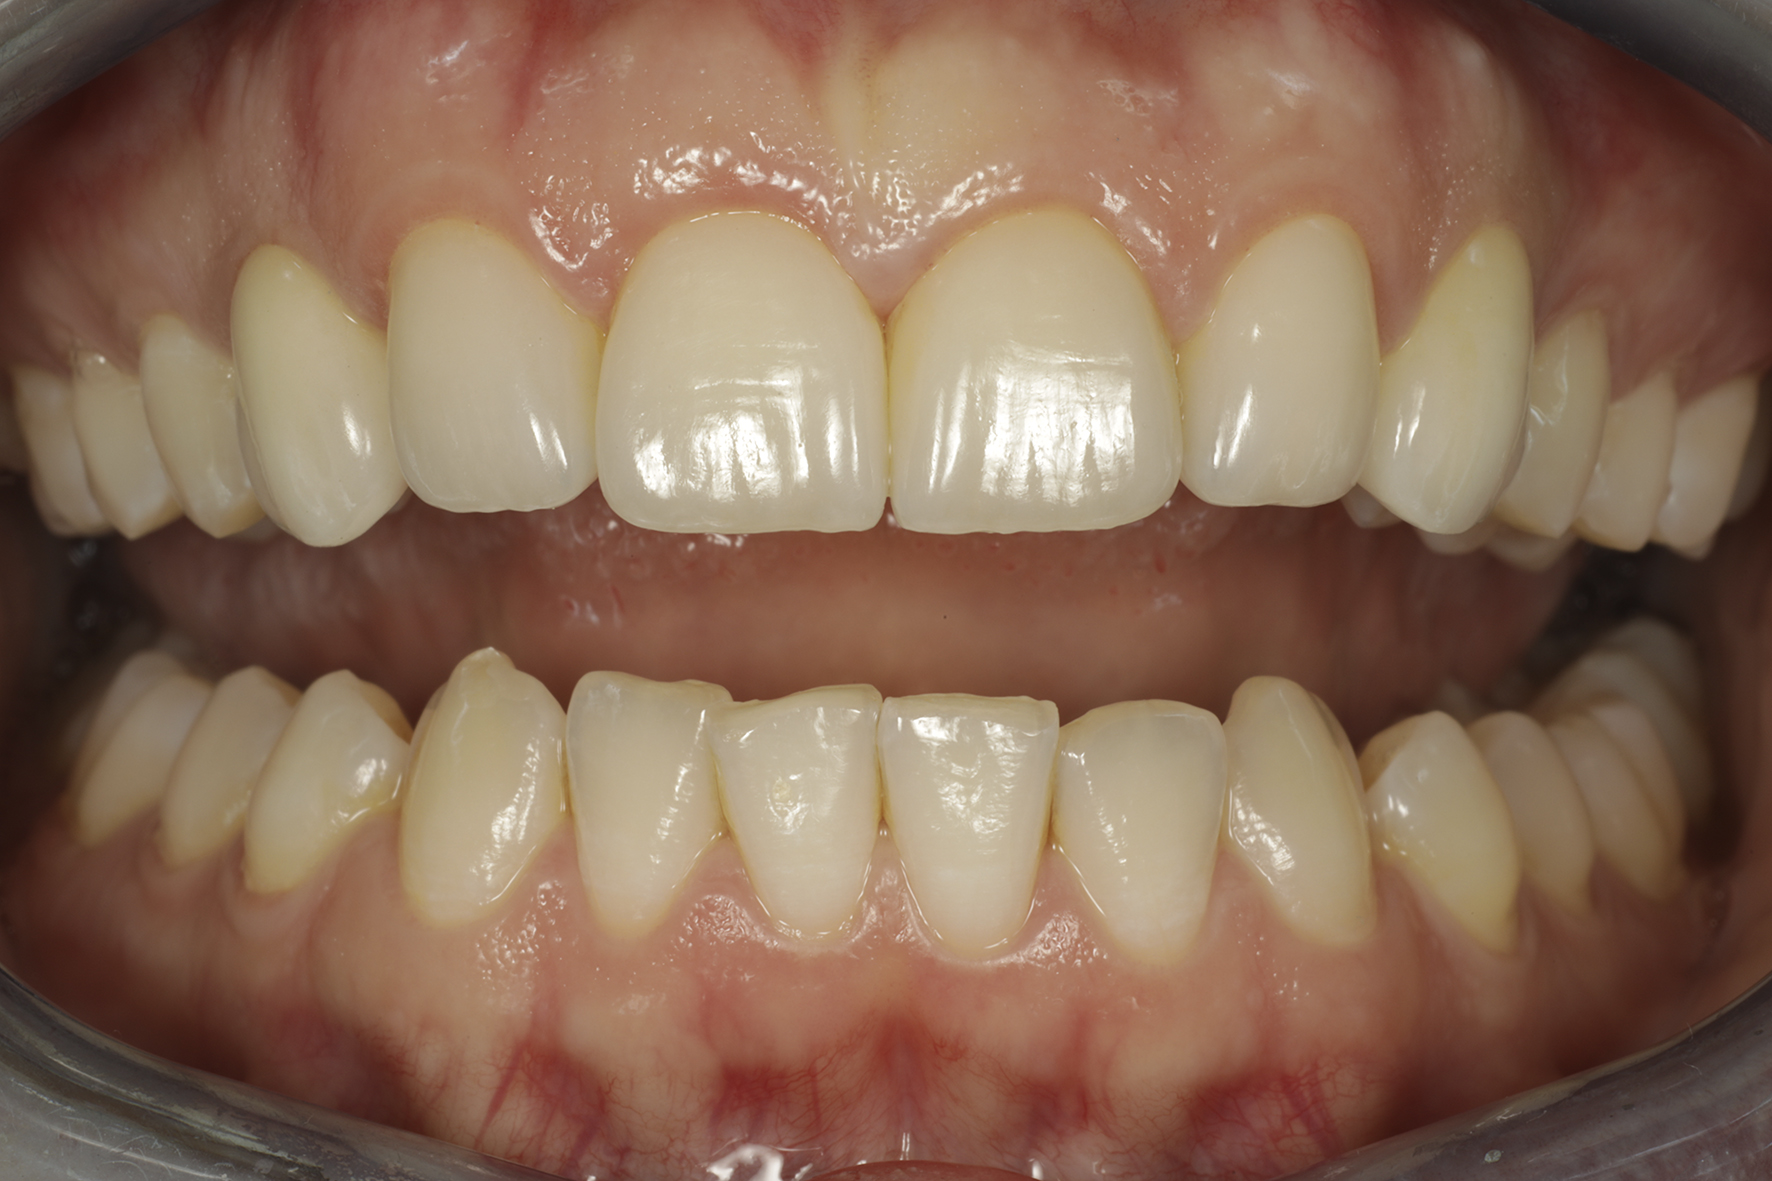

Lopputilanne 1/4. Implanttikruunut kulmahampaissa sekä ohuet keraamiset kuoret neljässä yläetuhampaassa paikoillaan.

Lopputilanne 2/4